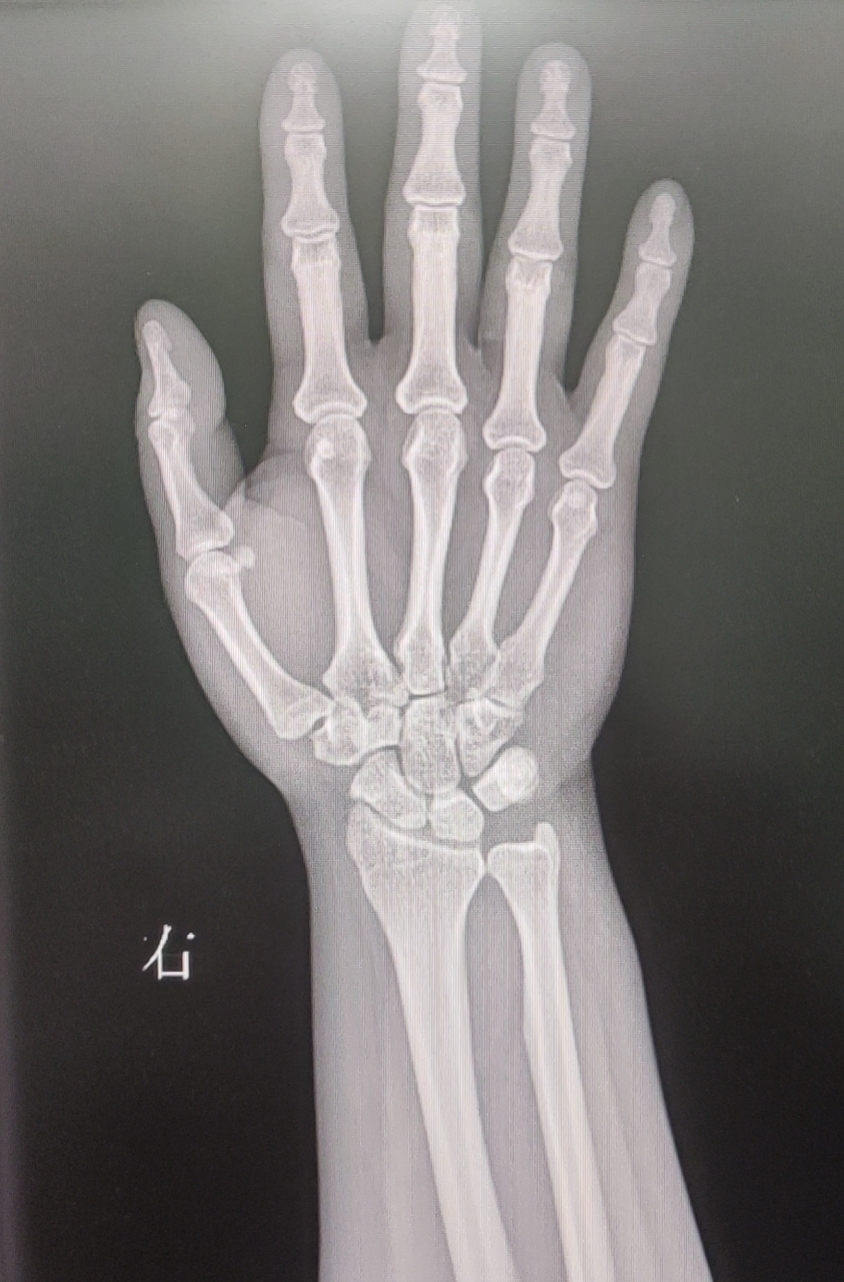

【影像】腕关节正位片见腕部骨质未见异常,尺骨正变异(-)。